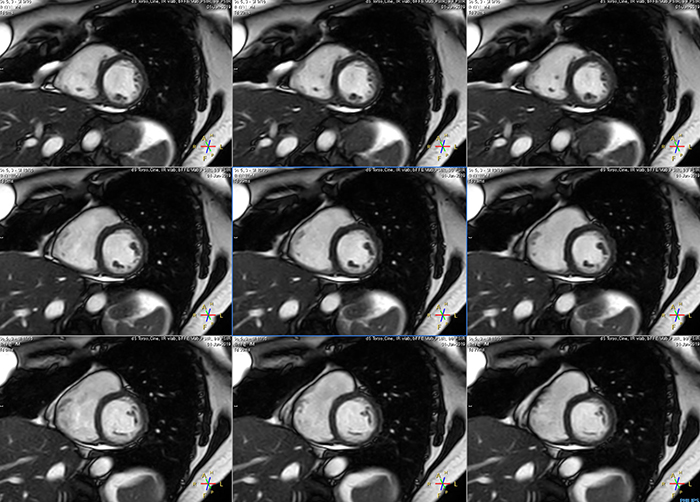

These are some images of a cardiac cine scan with a short breath-hold time. A high temporal resolution provides a smooth cine, which helps in assessing heart function. Ingenia Ambition.

Avila says that Compressed SENSE allows them to reduce breathhold time to 3 to 4 seconds in cardiac cine scans. “At the same time, we can now – based on cardiac frequency – obtain as many as 30 to 40 cardiac phases without sacrificing resolution, while before Ingenia Ambition, we were acquiring only 20 phases.

“This ability to use Compressed SENSE for obtaining higher temporal resolution translates to a much smoother cine. This allows me to better assess heart function,” Dr. Peña says.

The images obtained with Ingenia Ambition show large coverage and high uniform signal. More vessels are visible than in a previous exam of the same patient on Achieva. The movies show a higher temporal resolution in the Ambition acquisition than in a previous Achieva 1.5T exam. Both exams use a FOV of 300 mm and voxel height and width of 0.78 mm.